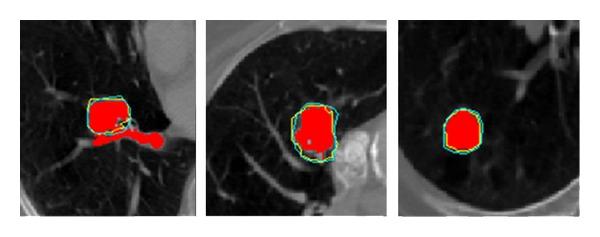

Accurate target delineation of CT image is a critical step in radiotherapy treatment planning. This paper describes a novel strategy for automatic contour propagation, based on deformable registration, for CT images of lung cancer. The proposed strategy starts with a manual-delineated contour in one slice of a 3D CT image. By means of feature-based deformable registration, the initial contour in other slices of the image can be propagated automatically, and then refined by active contour approach. Three algorithms are employed in the strategy: the Speeded-Up Robust Features (SURF), Thin-Plate Spline (TPS), and an adapted active contour (Snake), used to refine and modify the initial contours. Five pulmonary cancer cases with about 400 slices and 1000 contours have been used to verify the proposed strategy. Experiments demonstrate that the proposed strategy can improve the segmentation performance in the pulmonary CT images. Jaccard similarity (JS) mean is about 0.88 and the maximum of Hausdorff distance (HD) is about 90%. In addition, delineation time has been considerably reduced. The proposed feature-based deformable registration method in the automatic contour propagation improves the delineation efficiency significantly.

CT图像的精确靶区勾画是放射治疗计划中的关键步骤。本文描述了一种基于可变形配准的用于肺癌CT图像自动轮廓传播的新策略。所提出的策略从3D CT图像的一个切片中的手动勾画轮廓开始。通过基于特征的可变形配准,图像其他切片中的初始轮廓可以自动传播,然后通过主动轮廓方法进行细化。该策略采用了三种算法:加速鲁棒特征(SURF)、薄板样条(TPS)和一种自适应主动轮廓(Snake),用于细化和修改初始轮廓。使用了五个包含约400个切片和1000个轮廓的肺癌病例来验证所提出的策略。实验表明,所提出的策略可以提高肺部CT图像的分割性能。杰卡德相似度(JS)平均值约为0.88,豪斯多夫距离(HD)最大值约为90%。此外,勾画时间显著减少。所提出的基于特征的可变形配准方法在自动轮廓传播中显著提高了勾画效率。